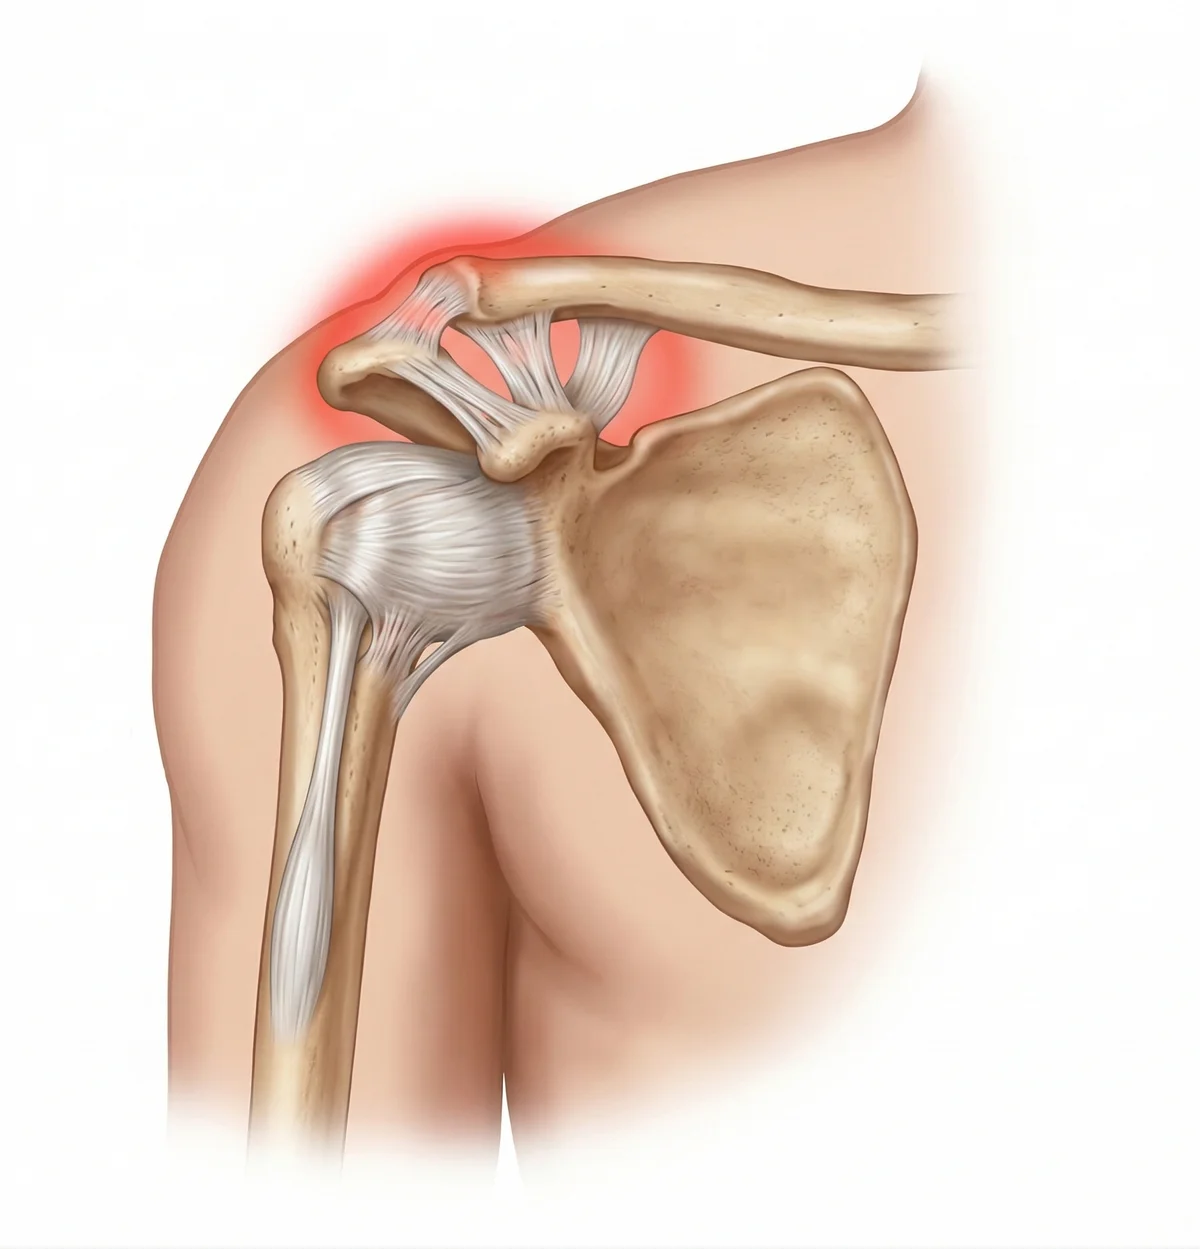

📢 什麼是肩鎖關節 (AC Joint)?肩膀的「屋頂」

我們的肩膀結構非常複雜,肩鎖關節位於肩膀的正上方,是鎖骨 最外側與肩胛骨的肩峰 相連的地方。它就像是肩膀的「屋頂」樑柱接口。

關鍵韌帶: 這個關節主要靠兩組韌帶固定:

• 肩鎖韌帶 (AC ligament): 提供水平方向的穩定。

• 喙鎖韌帶 (CC ligament): 提供垂直方向的穩定,是非常強壯的韌帶。 -

受傷機制: 最典型的原因是「肩膀側面直接著地」。這股衝擊力會把肩胛骨往下壓,但鎖骨卻被頸部肌肉拉住,這一上一下的剪力,就會把連接兩者的韌帶硬生生扯斷,導致鎖骨往上翹起。